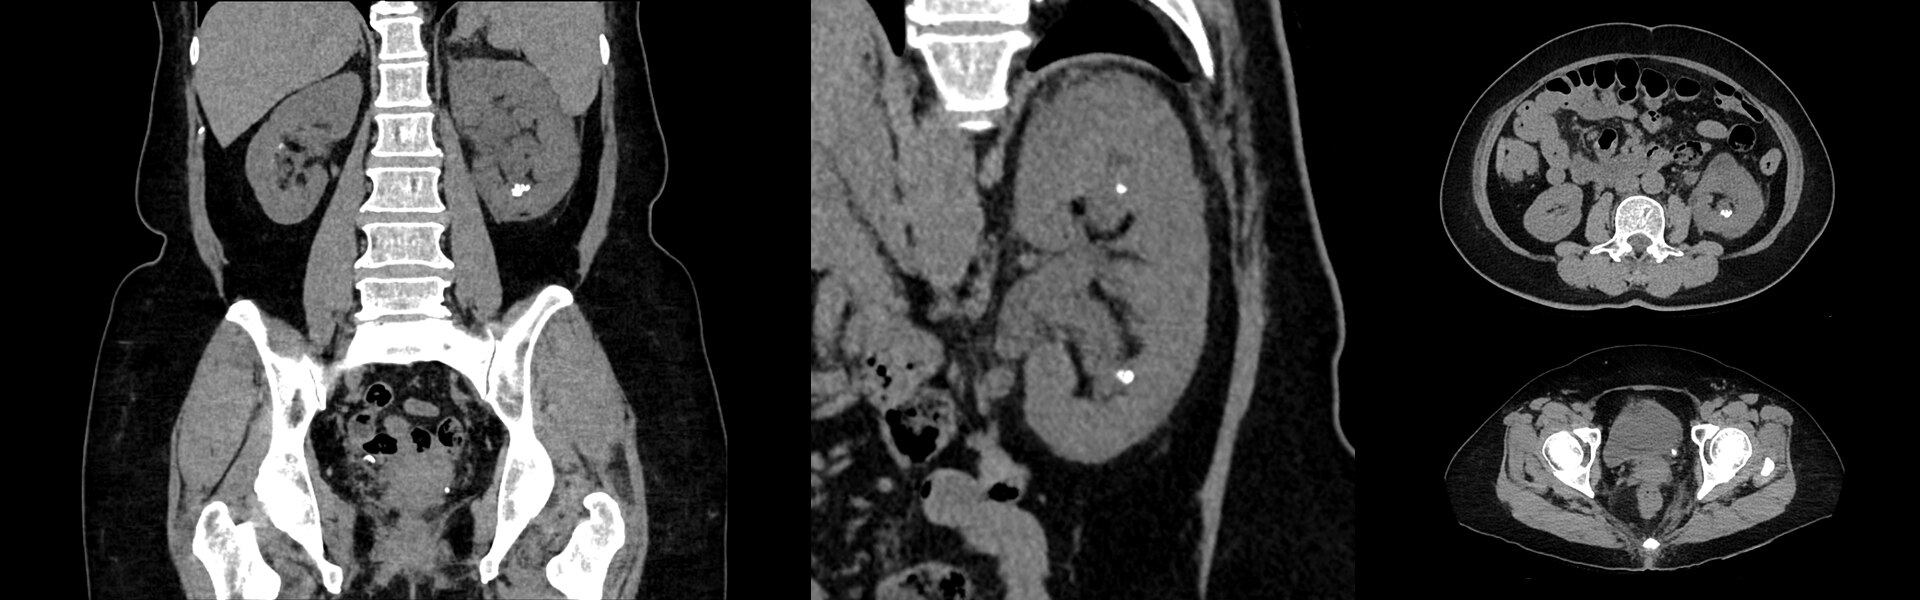

Digital detection, remastered

Discovery MI Gen 2 is engineered to deliver

- A scalable field-of-view

- A 60 percent increase in NECR1

- Exceptional sensitivity per cm (cps/kBq/cm)

- A 50 percent reduction in scan time1

- A 50 percent reduction in injected dose1

What does one more detector ring give you? A whole lot.